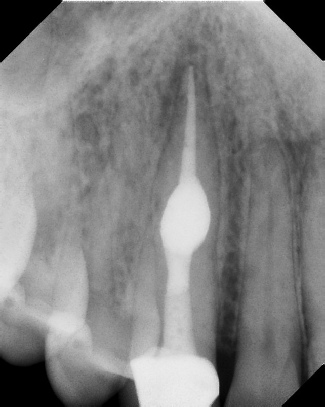

COMPLICATED ANATOMY LARGE LESIONS CALCIFIED CANALS PERFORATION / RESORPTION SEPARATED INSTRUMENTS SURGICAL CASES RETREATMENT / pOST REMOVAL OPEN APICES ACCESS THRU CROWNS Root Canal Case Portfolio

6 mos.